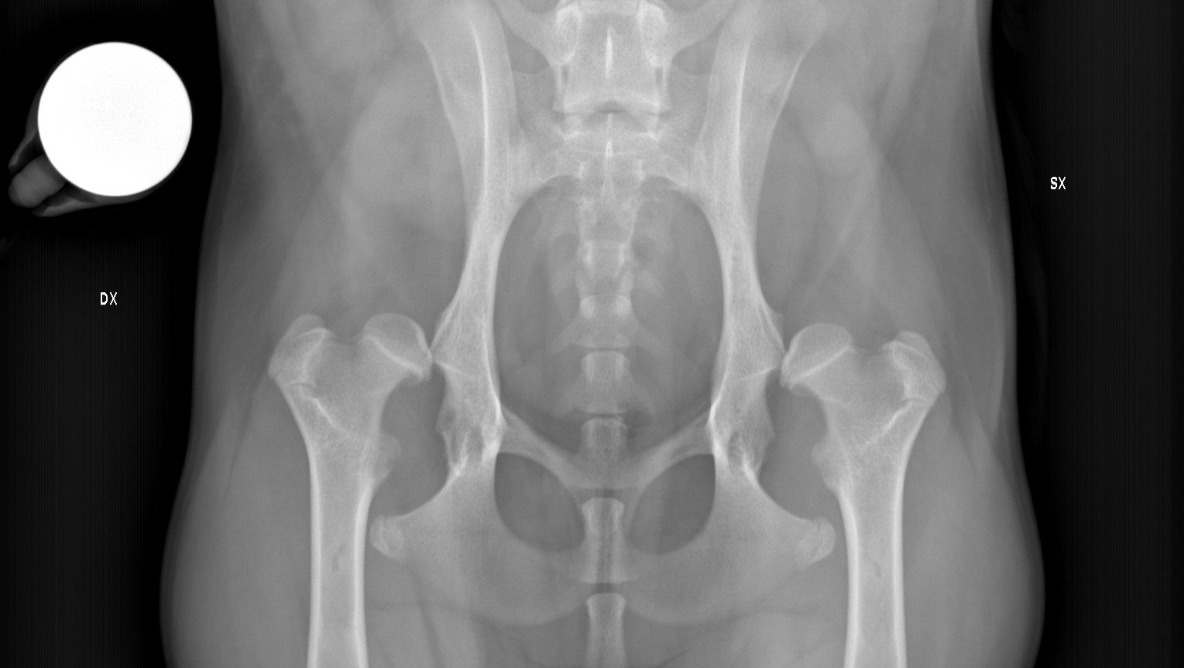

Luna e Linda sono due cucciole di cocker prese in carico dall'associazione Italian Cocker Rescue ODV nate con una gravissima malformazione delle anche, entrambe hanno una totale sublussazione, ovvero le teste dei femori completamente fuori dall'acetabolo.